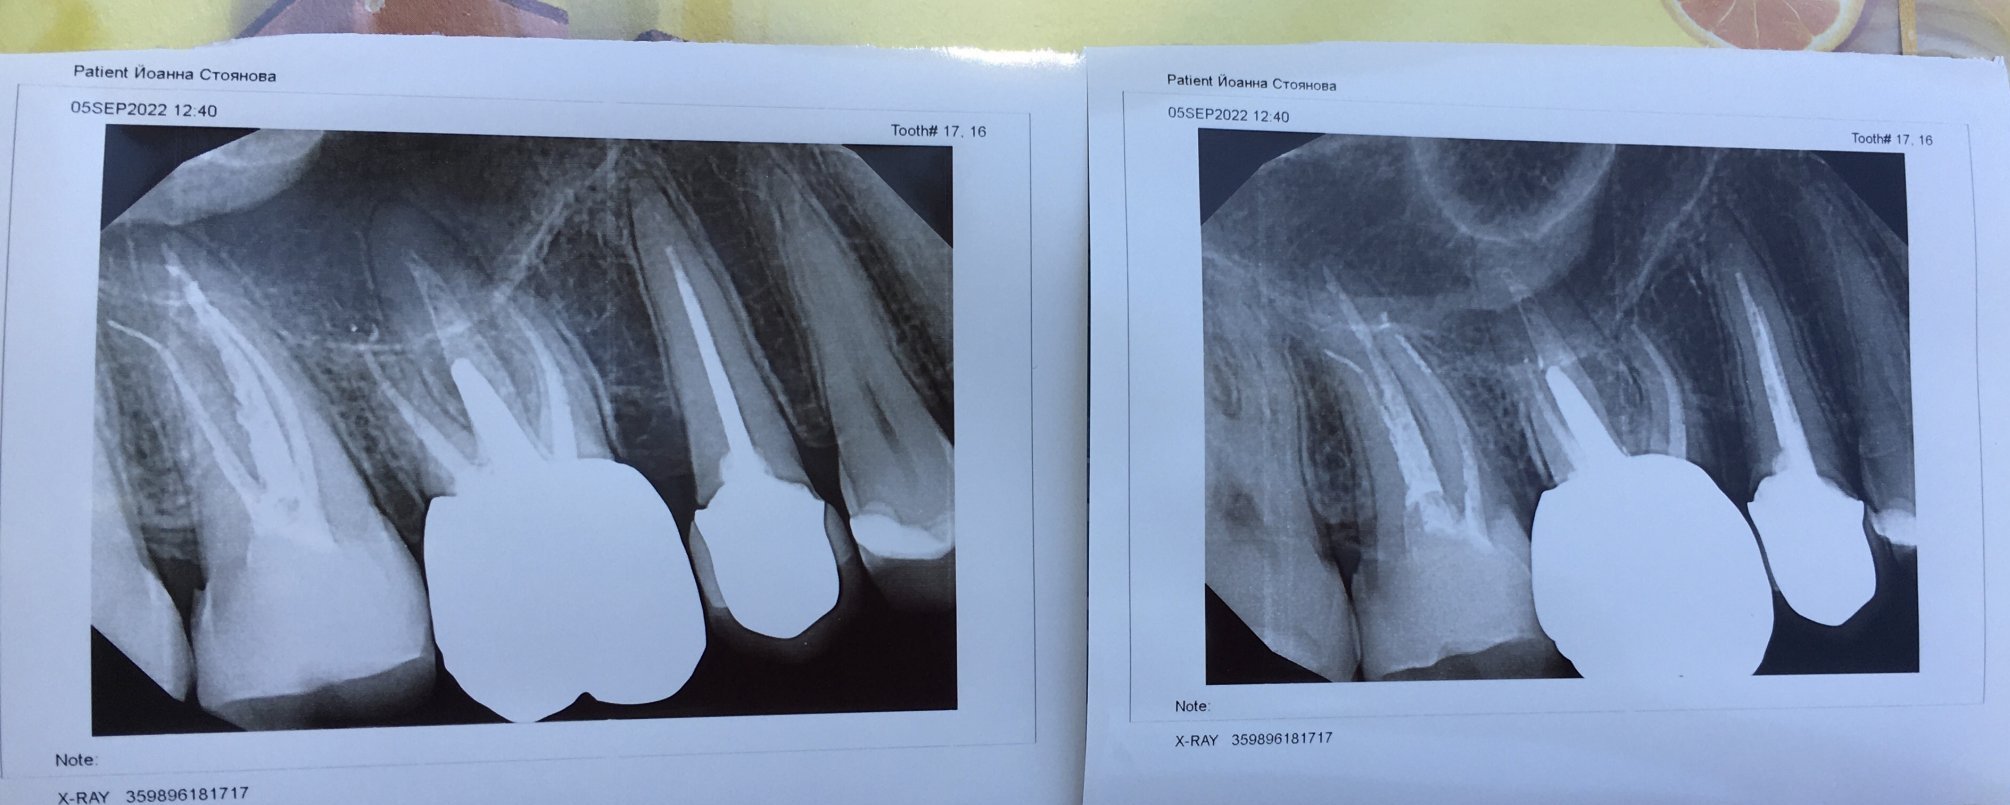

Здравейте, преди пет месеца умъртвиха седми горе вдясно. Не спира да боли, сега искат да му правят апикална остеотомия.

Прилагам снимка с молба за съвет: не може ли този зъб да се лекува по друг начин и защо е необходима тази процедура?

При мен се оказа, че са счупили инструменти при кореново лечение, както се вижда на снимките. Отрязаха част от двата корена. Но и досега имам болки в този зъб, при положение, че е девитализиран и не знаят защо. Докторът каза, че за пръв път му се случва болката да не е напълно изчезнала, та след два дни пак ще ходя. Операцията за мен беше неприятна. Така се отстраняват грануломи до колкото знам, за да се избегне ваденето на зъб, когато консервативното кореново лечение не е възможно. За кисти сигурно зависи от големината на кистата и какво е обхванала. Не съм запозната.